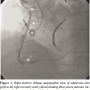

three tandem stenoses of 80–90% involving the proximal, mid, and distal segments of the saphenous vein graft (SVG) to the right coronary artery (Figure 1). PCI was performed successfully with deployment of three non-overlapping bare-metal stents without the use of a distal embolization protection device due to lack of sufficient distal space in the SVG for positioning. However, during final stent deployment, perforation of the distal segment of the SVG with extravasation

of contrast was noted (Figure 2). The patient remained hemodynamically stable while a 4.0 x 12 mm balloon was inserted for two prolonged inflations proximal to the site of the perforation in an effort to curb the leak. Meanwhile, anticoagulation was reversed with intravenous protamine, but the patient started clinically deteriorating, becoming hypotensive and hypoxic, requiring supplemental oxygen via face mask, intravenous neosynephrine and saline resuscitation for blood pressure support.